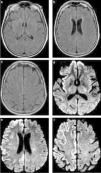

Encefalitis confirmada por estudio del líquido cefalorraquídeo. Se ilustra la utilidad particular de la difusión en el diagnóstico precoz de cuadros infecciosos virales. (a, b y c) Secuencia FLAIR que se interpreta como normal a los 3 días del inicio de los síntomas. (d, e y f) Secuencia de difusión del mismo estudio que muestra zonas extensas de restricción cortical a nivel del hemisferio derecho, con compromiso insular asociado, sin zonas de edema significativo ni efecto de masa.

En todas las infecciones virales, es común encontrar una elevada señal de DWI, con grados variables de restricción, en distintas topografías según el agente causal. Esto permite establecer la sospecha diagnóstica con adecuados niveles de sensibilidad18,30 (fig. 7). Inclusive, se ha descrito una elevada sensibilidad de la DWI para detectar zonas de actividad viral en los estadios precoces de la encefalitis en relación con el comienzo de la clínica. Esta se muestra con sectores de restricción cortical no identificados en otras secuencias (disociación clínico radiológica) (fig. 8).

Por último, debemos destacar el rol de esta secuencia en el diagnóstico de la leucoencefalopatía multifocal progresiva (LMP) en pacientes con VIH/sida. En los casos con inmunosupresión severa es fundamental establecer un diagnóstico basado en el estudio por proteína C reactiva (PCR) del LCR y los hallazgos imagenológicos, en vistas a modificar el pronóstico inmediato31.

La LMP es una afección desmielinizante subaguda, producida por la reactivación del virus JC. Debido a su naturaleza progresiva y mal pronóstico, el tratamiento y la evaluación de la respuesta son primordiales31,32. Recientemente, múltiples estudios han utilizado la secuencia DWI para detectar las zonas de actividad en pacientes con LMP y monitorizar su respuesta al tratamiento18,33. En estos casos, las lesiones en la DWI se caracterizan por una señal baja en el centro y una señal elevada en la periferia, lo cual indica actividad. Esta es el área pasible de respuesta a la terapia con antirretrovirales34 (fig. 9).